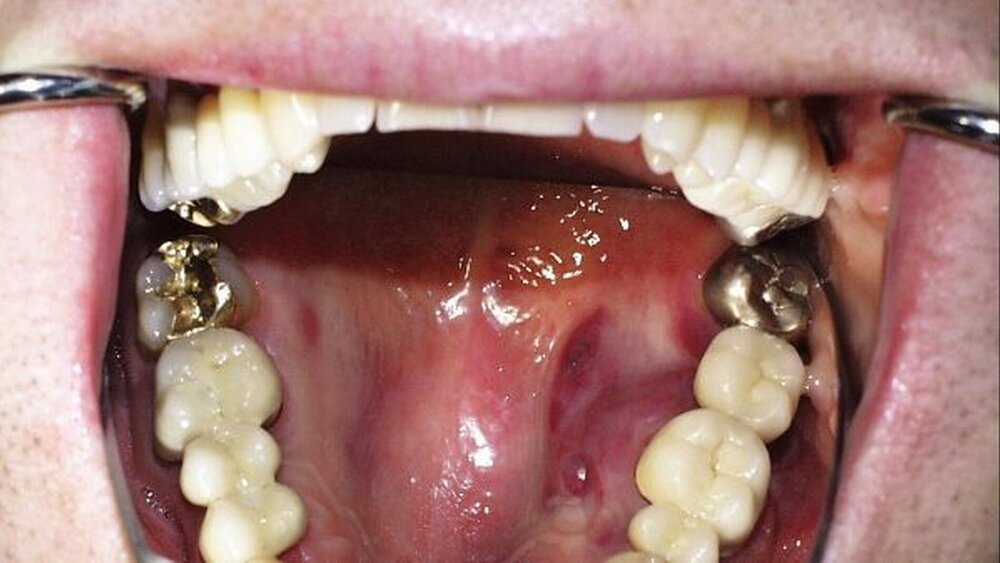

Weil die chronische Parodontitis neben der Zahnkaries die orale Haupterkrankung darstellt und somit auch bei Patienten ohne systemisch-pathologische Hintergründe in hoher Prävalenz auftritt, scheint vordergründig keine besondere Assoziation zur HIV-Infektion zu bestehen. Vor dem Hintergrund der oben beschriebenen immunologischen Alterationen weist sie jedoch besondere Merkmale auf, mit klinischen Implikationen hinsichtlich einer besonders engmaschigen Kontrolle und eines spezialisierten Betreuungskonzeptes. Besonders seit der Entwicklung antiretroviraler Therapieoptionen und der damit verbundenen gesunkenen Mortalität von HIV-Patienten treten die akuten Parodontalerkrankungen zugunsten chronischer Verlaufsformen in den Hintergrund [Jordan et al., 2007]: Eigene Untersuchungen konnten zeigen, dass eine konservative Behandlung der chronischen Parodontitis mit anschließender engmaschiger Erhaltungstherapie und überdurchschnittlicher häuslicher Plaquekontrolle im Vergleich zu einer HIV-seronegativen Kontrollgruppe zu vergleichbaren langfristigen Ergebnissen führen kann. Auch das Behandlungskonzept der One-stage Full-mouth Disinfection führte bei diesen Patienten zu keinen signifikanten Anstiegen in der postoperativen Körpertemperatur im Sinne einer Shwartzman-Reaktion, bedingt durch die massive Bakteriämie infolge der kurzzeitigen Abfolge der Wurzeloberflächenbearbeitung. Mikrobiologische Untersuchungen auf zehn parodontalpathogene Keime bis zu sechs Monate nach systematischer Parodontitistherapie stellten außerdem keine atypischen Verteilungsmuster dar [Jordan, 2005]. Allerdings wurden verstärkt kombinierte klinische Bilder durchlaufener NUG/NUP-Phasen im Zusammenhang mit ansonsten chronischer Parodontitis beobachtet, deren kosmetische Rekonstruktion kompliziert ist (Abbildung 1). Die unkompliziert verlaufende chronische Parodontitis bei HIV-Patienten kann vom parodontologisch tätigen Zahnarzt problemlos behandelt werden, wenn die grundsätzlichen Empfehlungen zur Infektionsprophylaxe zur Vermeidung einer Hepatitis-B-Infektion garantiert sind.

In der analytischen Epidemiologie weitgehend ungeklärt ist der Zusammenhang zwischen der signifikanten Zunahme von oralen HPV-Infektionen und antiretroviralen Therapien der HAART-Ära, die ohne intensive kurative Maßnahmen rasch in der gesamten Mundhöhle disseminieren und dann nur mit Mühe beherrschbar sind. Dennoch zeigte sich die Prävalenz bei der Einnahme antiretroviraler Therapiekombinationen inklusive Protease-Inhibitor (PI) doppelt erhöht im Vergleich zu PI-freien Regimen und um das Sechsfache erhöht im Vergleich zu therapiefreien Patienten [Greenspan et al., 2001] (Abbildung 2).